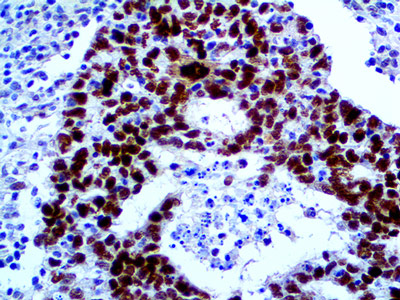

Anticorps BAP1 clone C4

La protéine BAP1 ou BRCA1 associated protein-1 (ubiquitin carboxy- terminal hydrolase) est une enzyme de dé-ubiquitination codée par le gène BAP1 situé sur le chromosome humain n°3 . BAP1 (BRCA1-associated protein 1) se lie au domaine N-terminal de BRCA1 et est considéré comme un gène suppresseur des tumeurs.